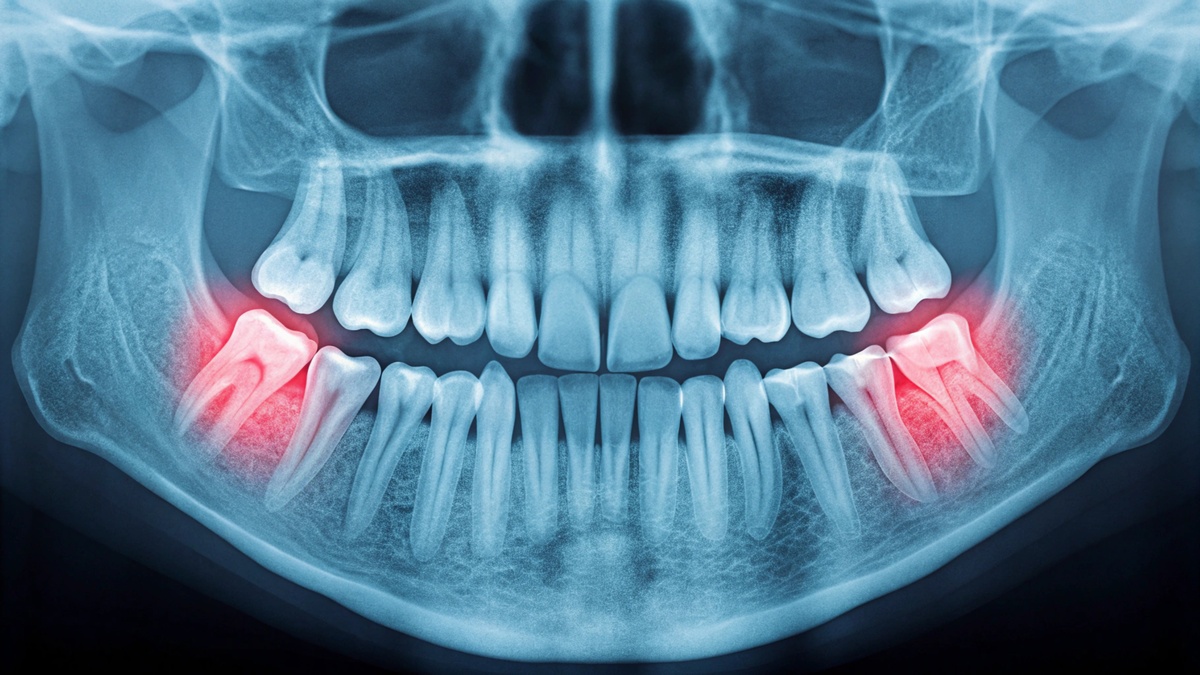

Wisdom teeth are the last molars to emerge, usually between ages 17 and 25. Because most mouths don’t have enough space for these extra teeth, they often become impacted, meaning they can’t fully break through the gums. When this happens, wisdom teeth can cause crowding, infection, cysts, damage to neighboring teeth, and chronic pain. Removing them before they cause problems is often the best approach.